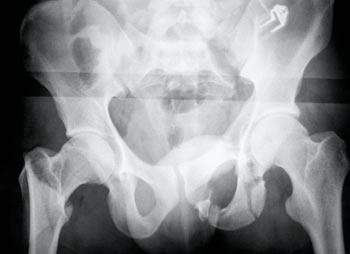

På akuttrommet var han fortsatt sirkulatorisk ustabil, til tross for massive infusjoner og blodtransfusjoner. Ved den initiale undersøkelse, utført av ortoped, ble bekkenet vurdert som stabilt. Det ble påvist tallrike andre ortopediske skader. Røntgen thorax og bekken ble tatt rutinemessig straks etter innkomst. Mens bildene ble fremkalt, ble pasienten undersøkt på nytt. Denne gangen fant man en stor diastase i symfysen. Røntgen av bekkenet viste betydelig diastase i symfysen, med avsprengt venstre acetabulum og venstre caput femoris luksert inn i bekkenet, i tillegg til flere andre frakturer (fig 1).

Bekkenfrakturen ble vurdert som sannsynlig årsak til pasientens ustabile sirkulasjon. Bekkenet og hele venstre underekstremitet ble stabilisert med ekstern fiksasjon, og blodtrykket stabiliserte seg. Seks måneder etter ulykken var pasienten oppegående, uten krykker, men med lett halting.